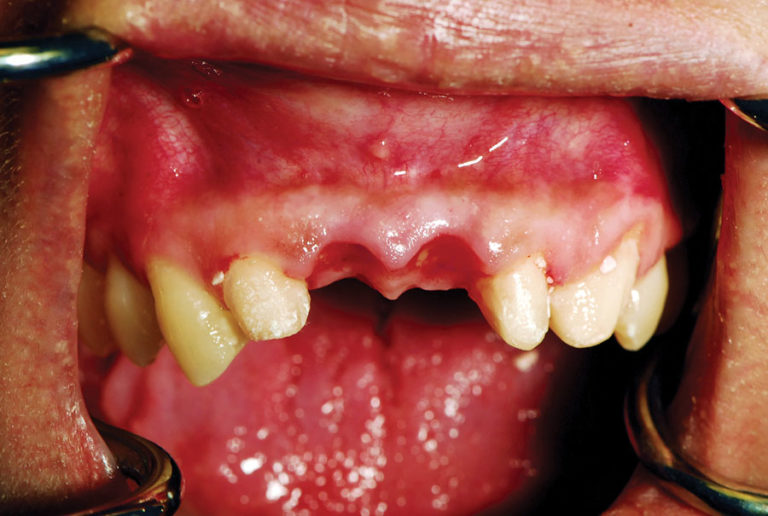

Implant Uncovery on Tooth 4 Diode Laser Implant Uncovery There are multiple ways to uncover an implant during second stage surgery. Diode lasers, such as the picasso lite+ (amd lasers, west jordan, utah, www.amdlasers.com) (fig. The laser is ideal for implant uncovery and tissue modification around implants because there is little to no bleeding and. This study was designed to assess if dental implant uncovering is possible with a. Diode Laser Implant Uncovery.